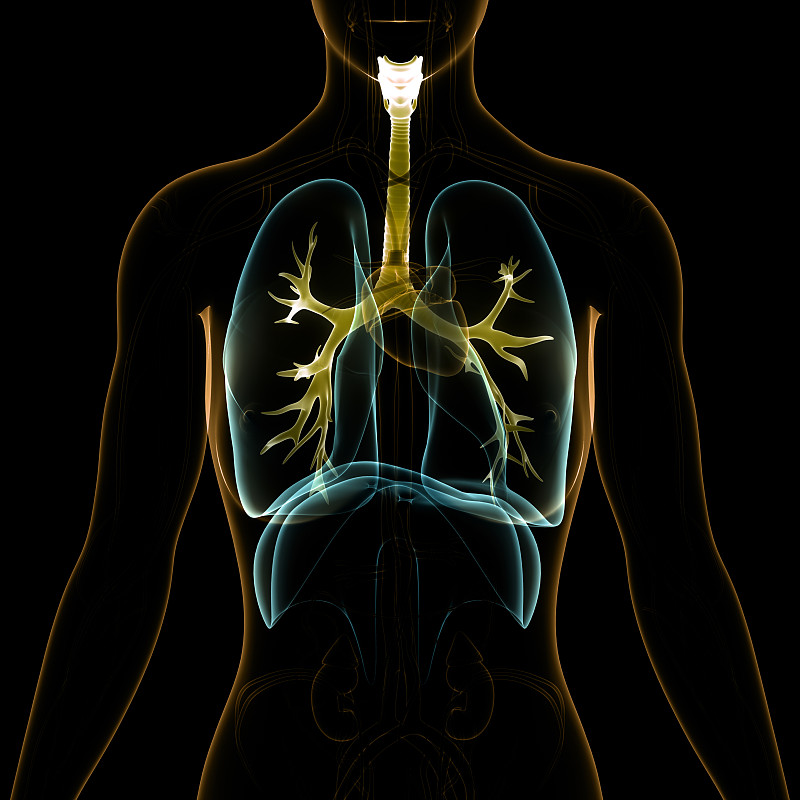

人体呼吸系统肺解剖学详情

JPG